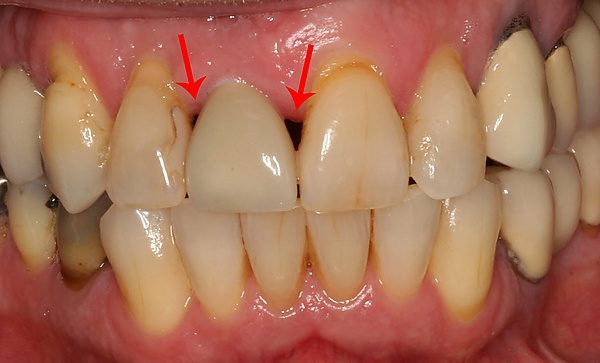

При утрате одного или нескольких зубов костная ткань в этом месте со временем истончается из-за отсутствия жевательной нагрузки, что ведёт к деформации челюстно-лицевой системы. Наличие имплантата обеспечивает адекватную нагрузку на кость челюсти подобно естественному корню зуба, поэтому истончения костной ткани не происходит. Каждый человек, который потерял один или несколько зубов в результате различных травм, болезней или разрушения зубов, имеют показания для имплантации зубов. Люди преклонного возраста также могут пройти процедуру имплантации, поскольку определяющим фактором её осуществления является скорее состояние здоровья, нежели возраст. Вопрос о том, возможно ли проведение дентальной имплантации, решается специалистом — стоматологом после тщательного медицинского обследования конкретного пациента и детального осмотра состояния его зубов.

Установка зубных имплантатов может вести к периимплантиту, который возникает из-за бактериальной флоры, попадающей на внешнюю поверхность имплантатов через зубной налет. Лечение данного заболевания проводили корейские исследователи с использованием титановой щетки.